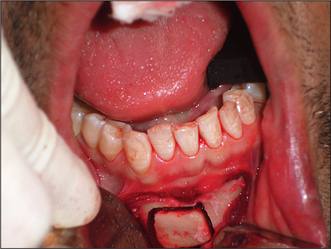

Most patients tolerate the loss of their natural teeth and subsequent denture wearing without difficulty. However, there may be extensive loss of alveolar bone after tooth extraction, resulting in an atrophic (flat or knife-edged) edentulous ridge (Fig. 11.4). In some patients this can make denture wearing difficult or uncomfortable. The prosthodontist may be able to modify a denture design to enhance its stability and retention, but this is not always possible. Surgery may therefore be required to enhance retention and stability of the prosthesis.

Fig. 11.4 This 32-year-old patient has difficulty in wearing a denture. The alveolar ridge has a ‘knife-edge’ profile, and there is a loss of sulcus depth.